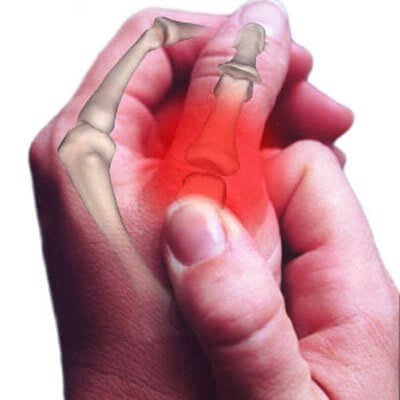

- Com’è risaputo, quando ci si rivolge ad un medico è perché “non se ne può più”. Il dolore alle mani è insostenibile, durante la notte si addormentano e cominciano ad apparire le prime deformazioni.

- Quando la malattia ha raggiunto questa fase, ormai non c’è più nulla da fare ed è impossibile frenarne il progredire. Appare chiaro, quindi, che la soluzione risiede nella precoce individuazione dei marcatori dell’artrite.